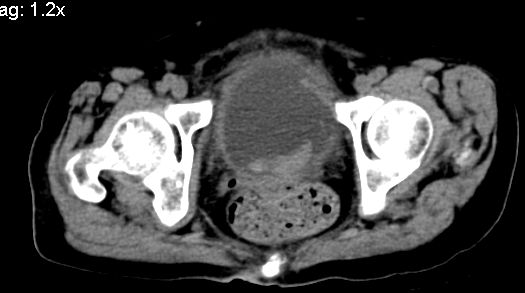

标题: CT10133:F、74岁,反复血尿10天。 [打印本页]

标题: CT10133:F、74岁,反复血尿10天。

补充一下,谢谢提醒!

1.膀胱后壁见不规则致密影,随体位改变,为膀胱内凝血块;

2.双侧输尿管下段扩张.输屎管结石可能大。建议作进一步检查。

双侧输尿管下端扩张,并膀胱内血凝块 输尿管下端结石